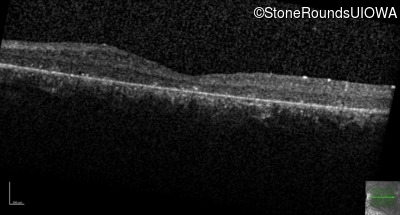

Age at visit: 8 years (Visit 2)

Age at visit: 9 years